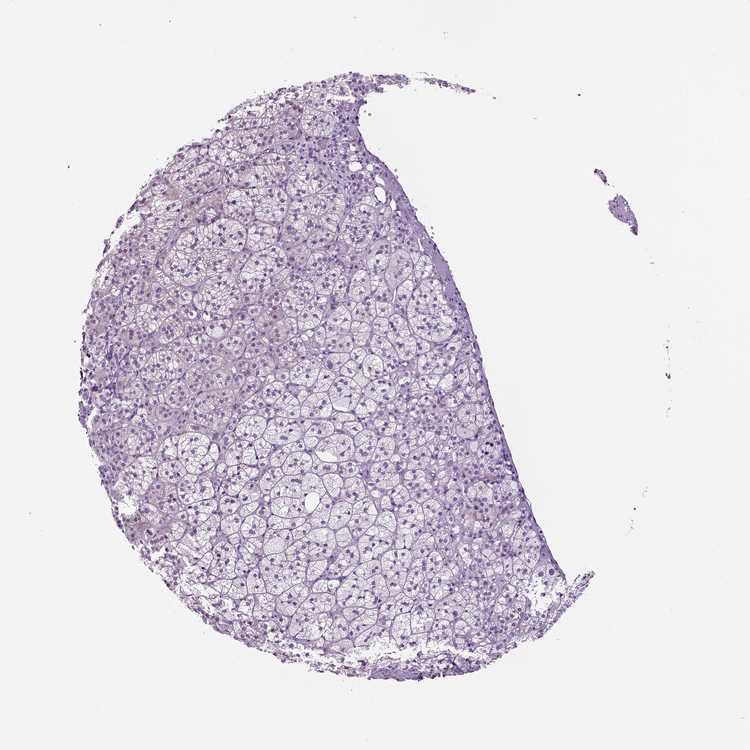

Adrenal gland

ADRENAL GLAND - Antibody stainingi

Antibody staining in the annotated cell types in the current human tissue is reported as not detected, low, medium, or high, based on conventional immunohistochemistry profiling in selected tissues. This score is based on the combination of the staining intensity and fraction of stained cells.

Each image is clickable and will lead to virtual microscopy that enables deeper exploration of all samples and also displays staining intensity scores, fraction scores and subcellular localization as well as patient and tissue information for each sample.

Antibody HPA053903Antibody HPA070647

Glandular cells LowNot detected